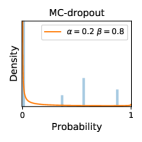

5.1 Distribution of Uncertainty Scores

Distribution of Uncertainty Scores Across Different Severity Levels As explained in Section 3, each uncertainty metric essentially defines an order/ranking among the data points. We conducted an analysis to better understand what data will be assigned high uncertainty under a particular uncertainty metric . Picking out the highest ranked data points (), we calculated the ratio of data points from each SL. Figure 4 summarizes the results as box plots for the Kaggle-DR and the Messidor-2 datasets; additional detailed statistics can be found in Table S.1 in the supplementary materials. From the plot and table, SL1 & SL2 examples account for a higher proportion among the top-ranked uncertain examples across the three ensemble methods. This finding matches our intuition that incipient disease examples (SL1 & SL2) are more likely to be considered uncertain by ensemble methods due to their ambiguity.

Comparing the three ensemble methods in Figure 4, the stacking ensemble method has the highest ratios of SL1 & SL2 data among the high-uncertainty examples it identified under both mean and var. TTA showed slightly better performance than MC-dropout but still falls behind the stacking ensemble method. Considering the fact that SL0 examples accounted for the majority of the dataset, the stacking ensemble method was much more precise (specific) in selecting truly ambiguous data points that were difficult to classify. From Figure 3, we can also see that the stacking ensemble method greatly outperformed the other two methods in finding false negatives under both mean and var uncertainty metrics.

In contrast, the MC-dropout method showed the worst overall performance among the three, as it can be seen from the high ratios of SL0 examples among the uncertain negatives in Figure 4. The histograms in Figure 2 provides another perspective to look into the phenomenon, where a decent proportion of MC-dropout model’s predictions on SL0 inputs entailed low confidence (far from 0 or 1), which from another angle explained why MC-dropout was less specific in terms of lower FNP; many no-DR inputs (i.e. SL0) were erroneously assigned high uncertainty by MC-dropout models.

It is still an open question why the evaluated MC-dropout networks signaled relatively high uncertainty on SL0 & SL3 & SL4 data that are less likely to be ambiguous. We conjecture that much of the “uncertainty” indicated by disagreement among test-time dropout samples actually reflects the stochastic nature of dropout networks rather than the real decision uncertainty associated with the data. It is worth noting that the MC-dropout model we evaluated was not weak per se; they all achieved above Area Under Curve (AUC) scores on test sets. The weakness of individual test-time samples (which explains their low-confidence predictions on SL0 & SL3 & SL4) might have been hidden when they are aggregated into an ensemble—a well-known advantage of ensemble learning. Our results suggested that the uncertainty information given by implicit ensemble methods such as MC-dropout and TTA might not be as reliable as that from explicit ensemble approaches (e.g., stacking ensembles). Similar findings on MC-dropout can be found in some previous papers [1].